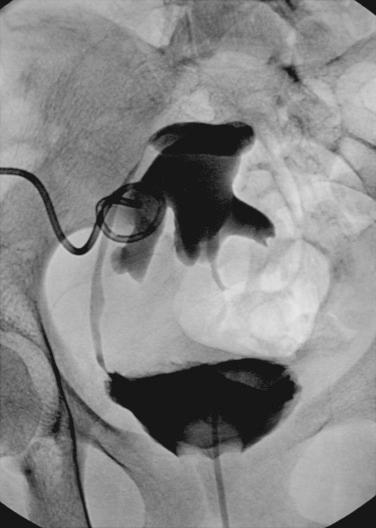

During the first 1 or 2 weeks after transplantation, obstruction usually is caused by a technical problem related to surgery (see Chapter 29 ). If a ureteral stent was placed at the time of surgery, it is highly unusual to have obstruction. Indeed, the incidence of major urologic complications after kidney transplant in patients who had a prophylactic stent placed during surgery is significantly lower compared with those who did not have a ureteral stent placed during the transplant. However, placement of ureteral stents during transplant carries a higher risk of infection so it is recommended that a sulfa-based antibiotic prophylaxis be administered to these patients. Possible explanations for obstruction are a twisted ureter or anastomotic narrowing. Generally, obstructions appear several weeks postoperatively, after the stent has been removed, and occur most frequently at the anastomosis between ureter and bladder. Usually, these obstructions can be crossed by a guidewire and dilated percutaneously by an interventional radiologist ( Fig. 14.1 ). If the nephrostogram shows a long (>2 cm) stricture, especially a proximal or midureteral stricture, it is likely to be a result of ischemia and is not usually amenable to balloon dilation, necessitating surgical repair ( Fig. 14.2 ). The operation of choice for a long stricture or one that has failed balloon dilation is ureteroureterostomy or ureteropyelostomy using the ipsilateral native ureter. The spatulated ends of the transplant and native ureters are anastomosed using running 5-0 absorbable suture. This anastomosis can be done over a 7 French double-J stent, which is left in place for 4 to 6 weeks. If no ipsilateral ureter is available, it may be necessary to use the contralateral ureter. If neither the ipsilateral ureter nor the contralateral ureter is available, alternatives include bringing the bladder closer to the kidney using a psoas hitch or fashioning a Boari flap, but these measures are seldom necessary. Another method is endoureterotomy; experience with this method is growing. Even if urinary obstruction is clinically silent (i.e., the patient is asymptomatic with a normal creatinine value), urinary obstruction manifested by dilation of the pelvis and calices on ultrasound should be treated because it ultimately leads to thinning of the renal cortex and loss of renal function. Urinary obstruction should be treated immediately to minimize damage to the transplanted kidney.

Fig. 14.1, This patient presented with an elevated creatinine level. Ultrasound showed pelvicaliceal dilation. (A) A percutaneous nephrostomy tube was placed, and the next day a nephrostogram was obtained. (B) The midureteral stenosis was crossed successfully with a guidewire, and the ureter was dilated with a balloon (the waist of the dilated balloon corresponds to the stricture). (C) Subsequently, a double-J stent was placed from the renal pelvis into the bladder across the dilated stricture.